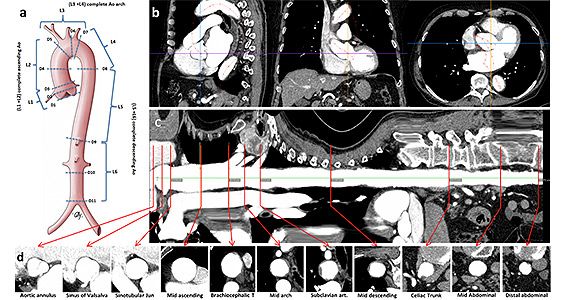

TAIPAN Tübingen Aortic Pathoanatomy Project

Leiter: Dr. med. Krüger

Dissektionen der Hauptschlagader (Aorta) stellen ausgesprochen kritische Notfälle der Herzmedizin dar. Folgen können ein Herzinfarkt, Schlaganfall, und damit Behinderung sein, in einzelnen Fällen führen Aortendissektionen trotz sofortig durchgeführter Notoperationen zum Tode. Die Erkrankung entsteht plötzlich und unvorhersehbar, eine wirkungsvolle Prophylaxe und Erkennung von Risikopatienten ist zum heutigen Tage nicht möglich. In einem groß angelegten Forschungsprojekt analysierten wir Computertomographien unserer Patienten der letzten 10 Jahre um Merkmale zu finden welche die Vorhersage einer Aortendissektion ermöglichen. Hierbei konnten wir die Längenparameter der aufsteigenden Aorta und des Aortenbogens als Prädiktoren für Aortendissektionen identifizieren. Wir entwickelten einen Algorithmus zur Risikovorhersage von Aortendissektionen.

Wir können zwischenzeitlich all jenen Patienten die wir in unserer Aortensprechstude [LINK] versorgen eine Diagnostik entsprechend dem genannten Algorithmus anbieten. Wir arbeiten auch weiter an der Verbesserung der Diagnostik, der Früherkennung und Prophylaxe gefährlicher Aortenerkrankungen.

- Kruger T, Oikonomou A, Schibilsky D, Lescan M, Bregel K, Vohringer L et al. Aortic elongation and the risk for dissection: the Tubingen Aortic Pathoanatomy (TAIPAN) projectdagger. European journal of cardio-thoracic surgery : official journal of the European Association for Cardio-thoracic Surgery 2017;51:1119-26.

- Lescan M, Veseli K, Oikonomou A, Walker T, Lausberg H, Blumenstock G et al. Aortic Elongation and Stanford B Dissection: The Tubingen Aortic Pathoanatomy (TAIPAN) Project. European journal of vascular and endovascular surgery : the official journal of the European Society for Vascular Surgery 2017

- Kruger T, Forkavets O, Veseli K, Lausberg H, Vohringer L, Schneider W et al. Ascending aortic elongation and the risk of dissectiondagger. European journal of cardio-thoracic surgery : official journal of the European Association for Cardio-thoracic Surgery 2016.

- Kruger T, Sandoval Boburg R, Lescan M, Oikonomou A, Schneider W, Vohringer L et al. Aortic elongation in aortic aneurysm and dissection: the Tubingen Aortic Pathoanatomy (TAIPAN) project. European journal of cardio-thoracic surgery : official journal of the European Association for Cardio-thoracic Surgery 2018